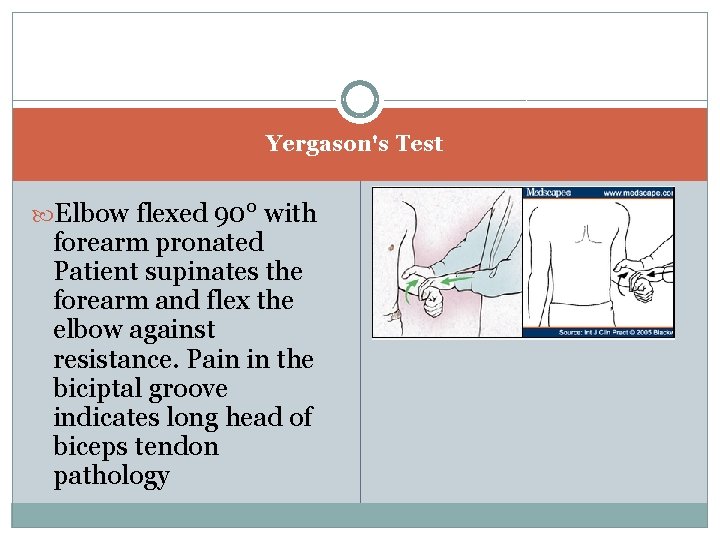

a Yergason's Test Elbow flexed 90° with forearm pronated Patient supinates the forearm and flex the elbow against resistance. Pain in the biciptal groove indicates long head of biceps tendon pathology